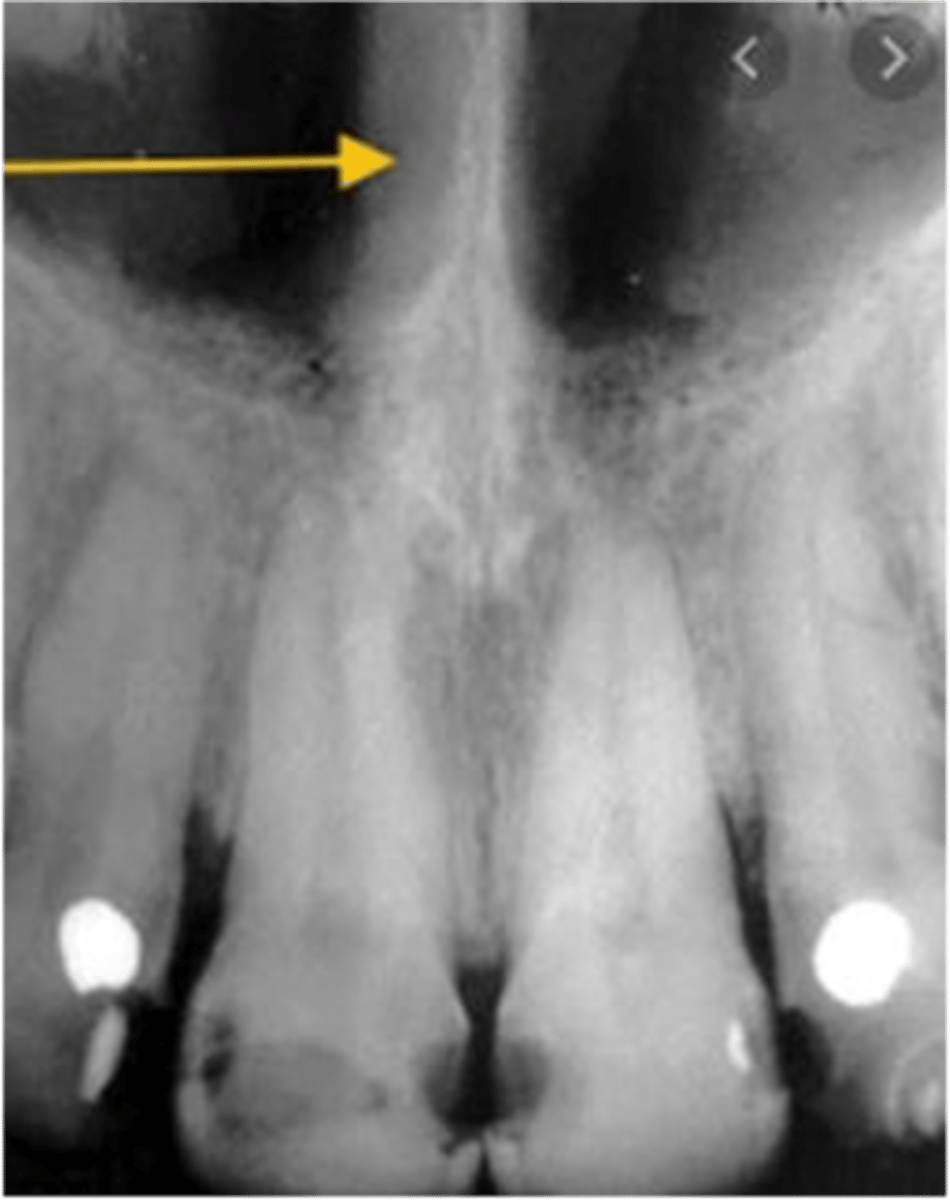

Median palatal suture

What is the radiolucent structure seen here?